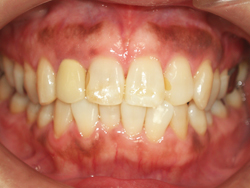

症例1 ・・・約10年間ほとんど変化ありません。

症例2 ・・・来院回数2回で、下の歯2から2を、講演10日後に控えた患者様からのご要望にお答えしました・・・。

一日で行っております。歯は削っておりません・・・。

症例1

症例1 ・・・禁煙後レーザー治療を行いました。後にホワイトニングを含めた審美治療を行います。